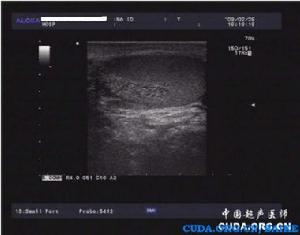

睪丸實質內表現出大小不等的無回聲區,占據整個睪丸的1/3或2/3,主要分布在睪丸縱膈鄰近區域,無回聲區域內無血流色彩充填,鄰近睪丸組織血流色彩正常。白膜呈正常組織回聲,不受累、不均厚。